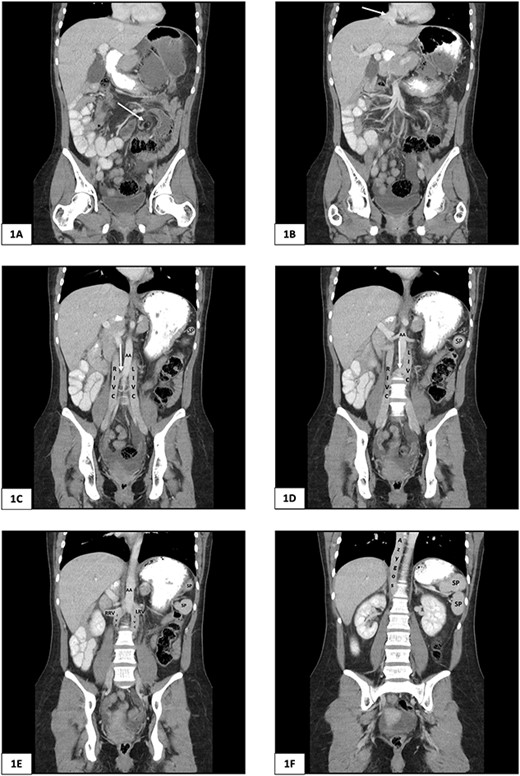

Computed tomography of the abdomen and pelvis of 25-year-old female presenting with caecal volvulus, intestinal malrotation, duplicate inferior vena cava, azygos continuation of the IVC, and fragmentation of the spleen. RIVC, right inferior vena cava; LIVC, left inferior vena cava; RRV, right renal vein; LRV, left renal vein; AA, abdominal aorta; SP, splenic fragment. (A) Arrow indicates mesenteric whirl sign. (B) Arrow indicates suprahepatic IVC draining from right, middle, and left hepatic veins into the right atrium. (C) and (D) Arrow indicates communicating vein from right IVC to left IVC.

There was malrotation of the gut with all colon on the left side and most of the small bowel on the right side of the abdomen (Fig. 2A). There was duplication of the infrarenal IVC, interruption of the suprarenal IVC with azygos continuation (Fig. 1C–F). A left-sided IVC draining venous blood from the left common iliac vein was present which drained into the left renal vein, while the right IVC drained blood from the right common iliac vein into the right renal vein. A retroaortic communication draining blood from the right IVC into the left IVC was also noted. From the renal veins all venous return was via the azygos vein to the superior vena cava with interruption of the suprarenal IVC. A suprahepatic IVC draining blood from the middle, left, and right hepatic veins into the right atrium was present (Fig. 1B). The spleen was divided into five distinct fragments, all within the splenic fossa and each supplied by an individual branch of the splenic artery (Figs 1 and 2).